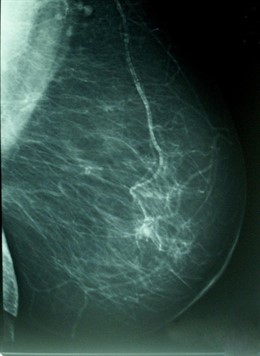

Cáncer De Mama, Densidad Mamográfica

El sistema de salud de Castilla-La Mancha dispone de programas de cribado, como el de Diagnostico Precoz de Cáncer de Mama, y de protocolos específicos de diagnóstico y de tratamiento contra el cáncer, ha informado la Junta en nota de prensa.

Gracias al programa de cribado, cerca del 70 por ciento de las mujeres entre 45 y 70 años de Castilla-La Mancha se realizaron una mamografía el pasado año. Así, dentro de la campaña 2011-2012 un total de 282.853 mujeres fueron citadas, lo que supone un incremento de un 3% respecto a la anterior.

Estos programas son especialmente importantes ya que la mortalidad por cáncer se puede reducir si los casos se detectan y tratan precozmente. En los programas de cribado se realizan pruebas en poblaciones sanas para detectar signos de cáncer y remitir rápidamente a esos pacientes a servicios donde se pueda establecer el diagnóstico e iniciar el tratamiento.